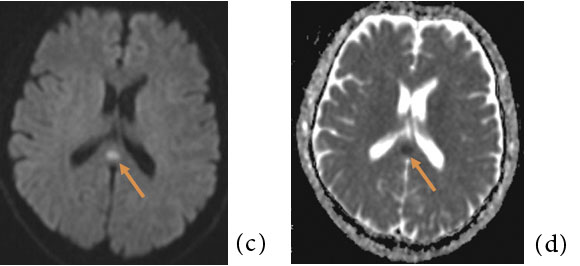

MRI では、T2 強調像および拡散強調像にて 脳梁膨大部中間層に円形もしくは卵円形の高信 号を呈する領域を認め、T1 強調像にて淡い低信 号もしくは等信号を呈する(Fig.1)。ADC map では一過性病変であるにも関わらず、急性期脳 梗塞など細胞障害性変化を来す疾患と同様に病 変部のADC 値は低下している。よって同じ一 過性病変である、高血圧脳症などいわゆるposterior reversible encephalopathy syndrome (PRES)や、高地脳症などにおける血管原性浮 腫とは異なる病態が存在する。このADC 値低 下の原因については軸索の表面を覆うミエリン 鞘の分離によって生じる軸索内浮腫2)が最も考 えられているが、まだコンセンサスは得られて いない。Takanashi らはMERS 患者に共通して 低ナトリウム血症を認めたと報告しており3)、 特に感染症においては嘔吐や下痢に伴う電解質バランスの破綻も関与している可能性がある4)。 異常信号は脳梁の他の部位や、白質に左右対称 性に及ぶこともある。通常は可逆性だが、時に 不可逆性の場合もある。造影MRI にて造影増強効果は認めない1) 5)

Fig.1 50 歳代、男性。軽度の意識レベル低下を認めたためにMRI が施行された。

(a,b):脳梁膨大部に卵円形の淡いT2WI 高信号、T1WI 低信号域を認める (矢印)。明らかなmass effect は認められない。

(c, d):同病変は拡散強調像にて高信号(矢印)、ADC map にて低値を示し (矢印)、拡散低下が示唆される。